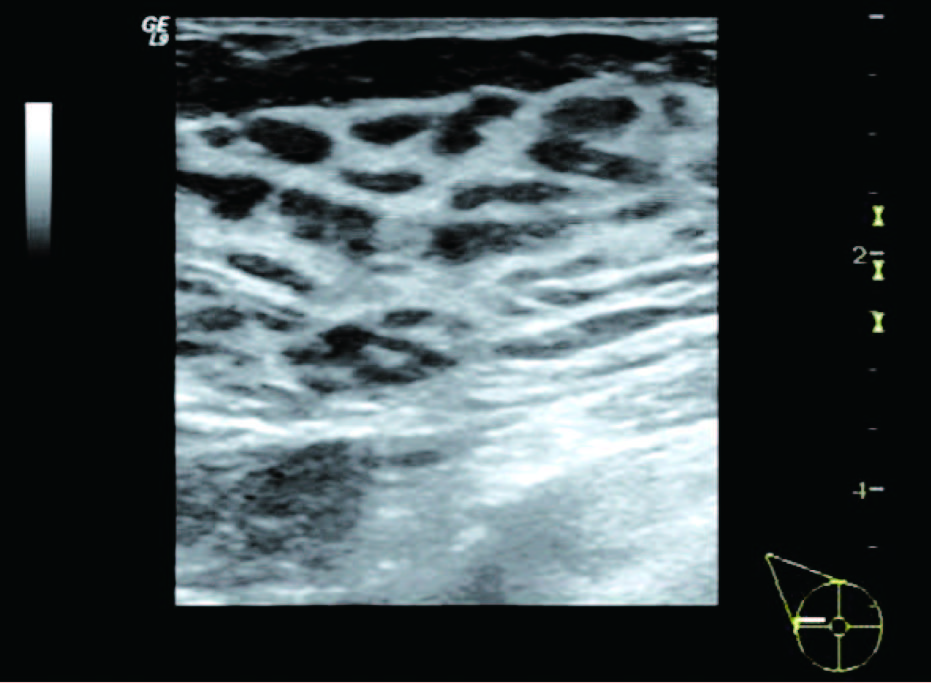

(1)单纯增生型:表现为乳腺腺体不同程度增厚,腺体内部结构稍紊乱,分布欠均匀,可见散在或弥漫分布的形态欠规则、边界欠清晰、大小不一的低回声区与稍高回声区相间,呈现“豹纹征”声像改变。可伴有钙化灶,钙化为较粗大沙砾状、杆状或小弧状,分布于乳腺局部,也可弥漫分布于整个乳腺,其内未见彩色血流信号或少许点状彩色血流信号,无明显囊肿及结节。